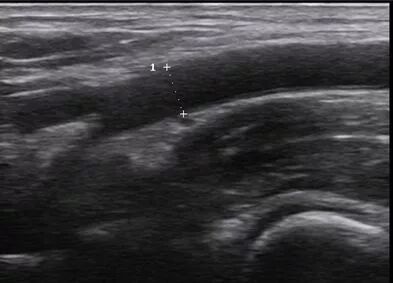

取样容积的大小

上图中那个类似“=”的小框框就是所谓的取样容积,也就是说落在这个框里的信号才会被采集,一般认为取样容积的大小为血管直径的50-70%,也就是大概2/3左右。